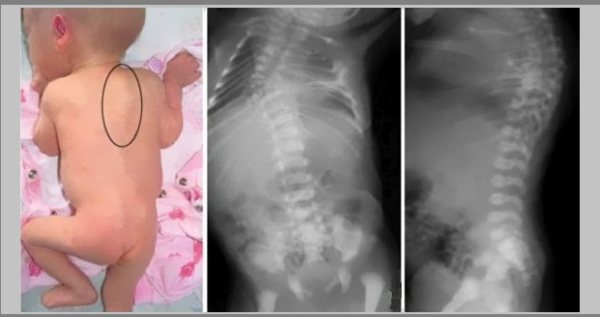

У данной комбинированной деформации заметные симптомы. Она может являться врожденной, и тогда диагностировать кифосколиоз можно уже у младенца в возрасте от шести месяцев (начинает сидеть и становиться на ноги). Если недуг приобретенный, на раннем этапе сложно его распознать, но можно диагностировать патологии, способные стать его причиной.

Кстати. При врожденной форме обнаружить заболевание сразу после рождения удается редко. Обычно его находят, когда ребенку исполняется полгода. Чтобы искривления стали заметны, необходимо начало периода, когда малыш садится и встает на ножки, используя их в качестве опоры. Тем не менее, кифосколиоз, в степени три и выше может быть выявлен непосредственно после рождения.

В случае с врожденной болезнью, патологию у ребенка можно заметить примерно в 6 месяцев от рождения и изначально только в вертикальном положении. При отсутствии лечения кифосколиотическая деформация увеличивается.

Симптоматика

Даже будучи врожденным, кифосколиоз, как правило, раньше возраста шесть месяцев не диагностируется. Чаще заболевание обнаруживается ближе к одному году. Начинается визуальное проявление с того, что на спине младенца появляется и становится заметным горбик.

Почему практически невозможно обнаружить кифосколиоз у младенца? Потому что на первоначальной стадии визуально заметить искривление возможно лишь, когда он занимает вертикальное положение, то есть сидит или стоит. Если младенец лежит, оно исчезает. Далее, когда заболевание прогрессирует, искривление становится стойким и перестает зависеть от вертикального или горизонтального положения.